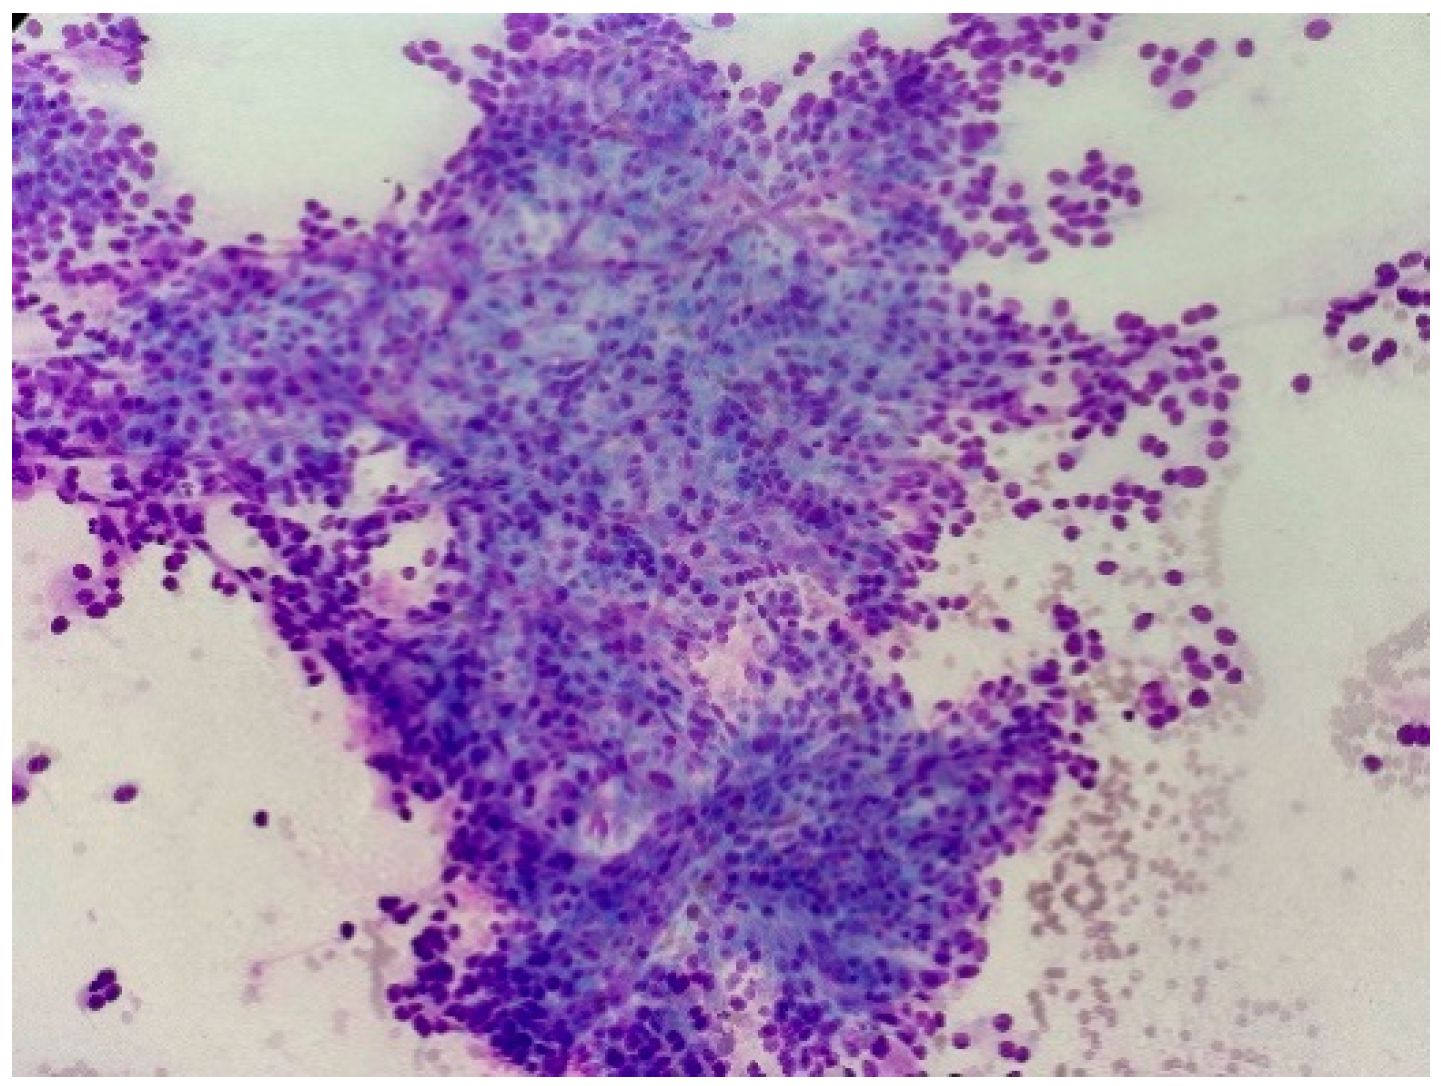

EUS fine-needle aspiration cytology (FNAC) showed cellular smears with numerous abnormal cells appearing with a high nuclear–cytoplasmic ratio, salt and pepper chromatin with rare nuclear molding, and some markedly enlarged nuclei. Scant lymphocytes are seen in the background (Figure 1). Immunohistochemistry performed on the cell block showed tumor cells positive for CD56 and synaptophysin, and negative for CD117 and CD34. A diagnosis of neuroendocrine tumor was made and a resection was advised.

Figure 1. Fine needle aspiration cytology preparation shows sheets of cells arranged in nest and groups. The neoplastic cells show round to oval hyperchromatic nucleus (Giemsa stain image, 20×).